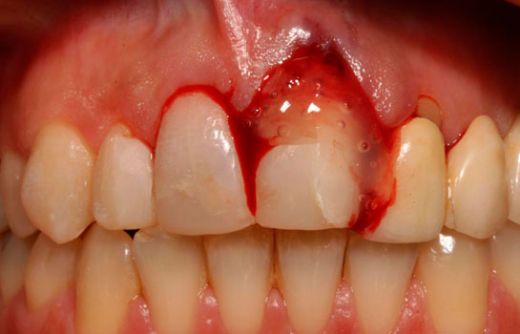

İlk İlişki Sonrası Kanama